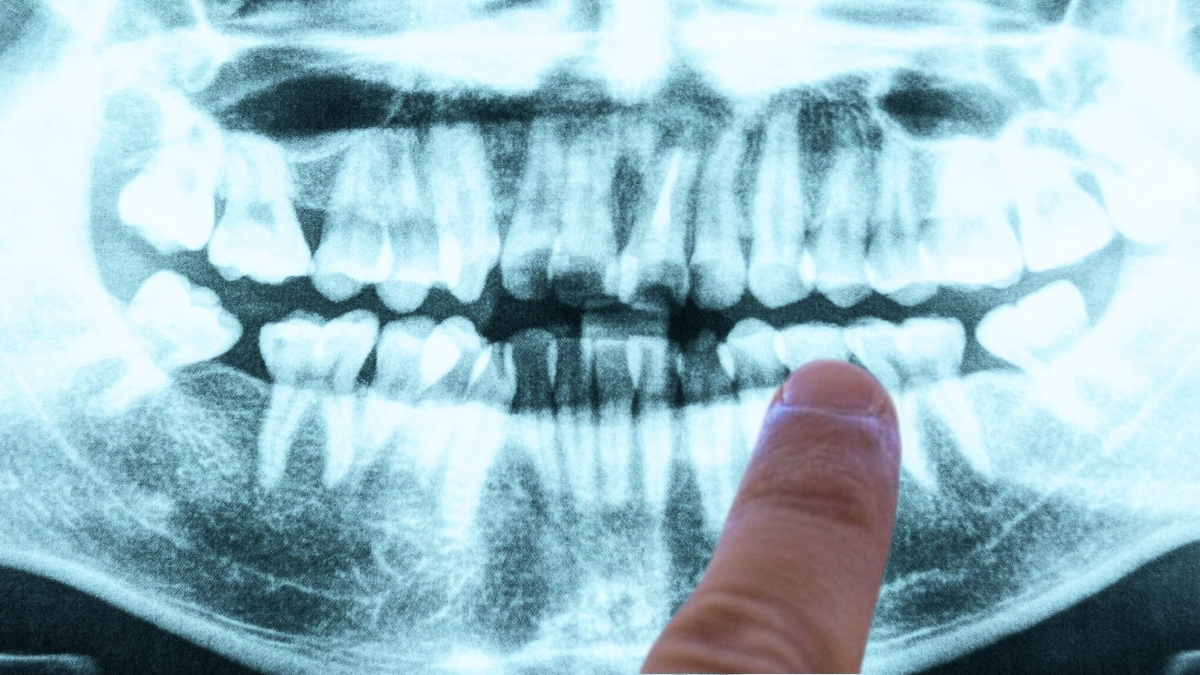

A fascinating study from 2019 pointed towards a possible bacterial culprit related to Alzheimer’s, surprisingly from gum disease.

In this study led by Jan Potempa, a microbiologist at the University of Louisville, researchers found Porphyromonas gingivalis, the pathogen responsible for chronic periodontitis, in the brains of deceased Alzheimer’s patients.

In experiments involving mice, they discovered that an oral infection with the pathogen resulted in bacteria colonizing the brain and increased production of amyloid beta (Aβ), the proteins often linked to Alzheimer’s.

Additionally, the researchers identified toxic enzymes called gingipains produced by this bacteria in the brains of Alzheimer’s patients, correlating with two separate disease markers: tau protein and ubiquitin.

Interestingly, they also found these toxic enzymes in the brains of individuals who had never been diagnosed with Alzheimer’s. This finding raises important questions: does gum disease lead to Alzheimer’s, or could dementia result in poorer oral hygiene?

The authors stated that their findings indicate brain infection with P. gingivalis isn’t merely a result of deteriorating dental care as dementia progresses but could be an early event explaining pathology in middle-aged individuals prior to any cognitive decline.